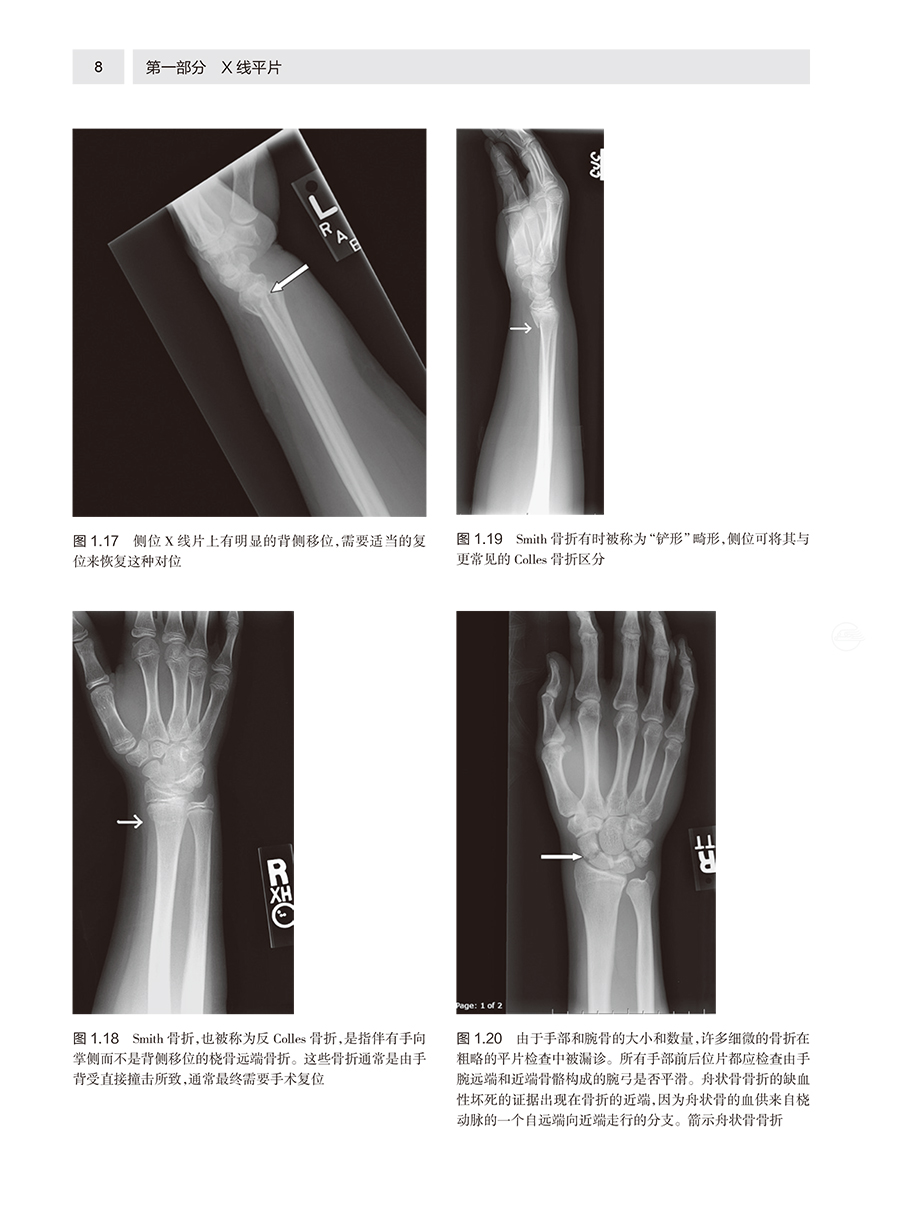

本书分为平片、超声、CT和MRI四部分。每部分依据检查部位组织编写,介绍了急诊影像常见的影像征象基础、影像检查的诊断性、成像陷阱和成像局限性,配有大量真实图像和线条图,内容简明精炼,是院前急救、医院急症室诊治和危重症监护病房等临床领域和急诊影像专业不可多得的资料。 本文介绍了临床急诊放射学的专业知识,包括X线平片、超声、计算机断层扫描、磁共振成像,介绍了各种技术的原理、特征及应用,并配合了大量的临床图片进行说明,给临床工作者提供了很有价值的参考。